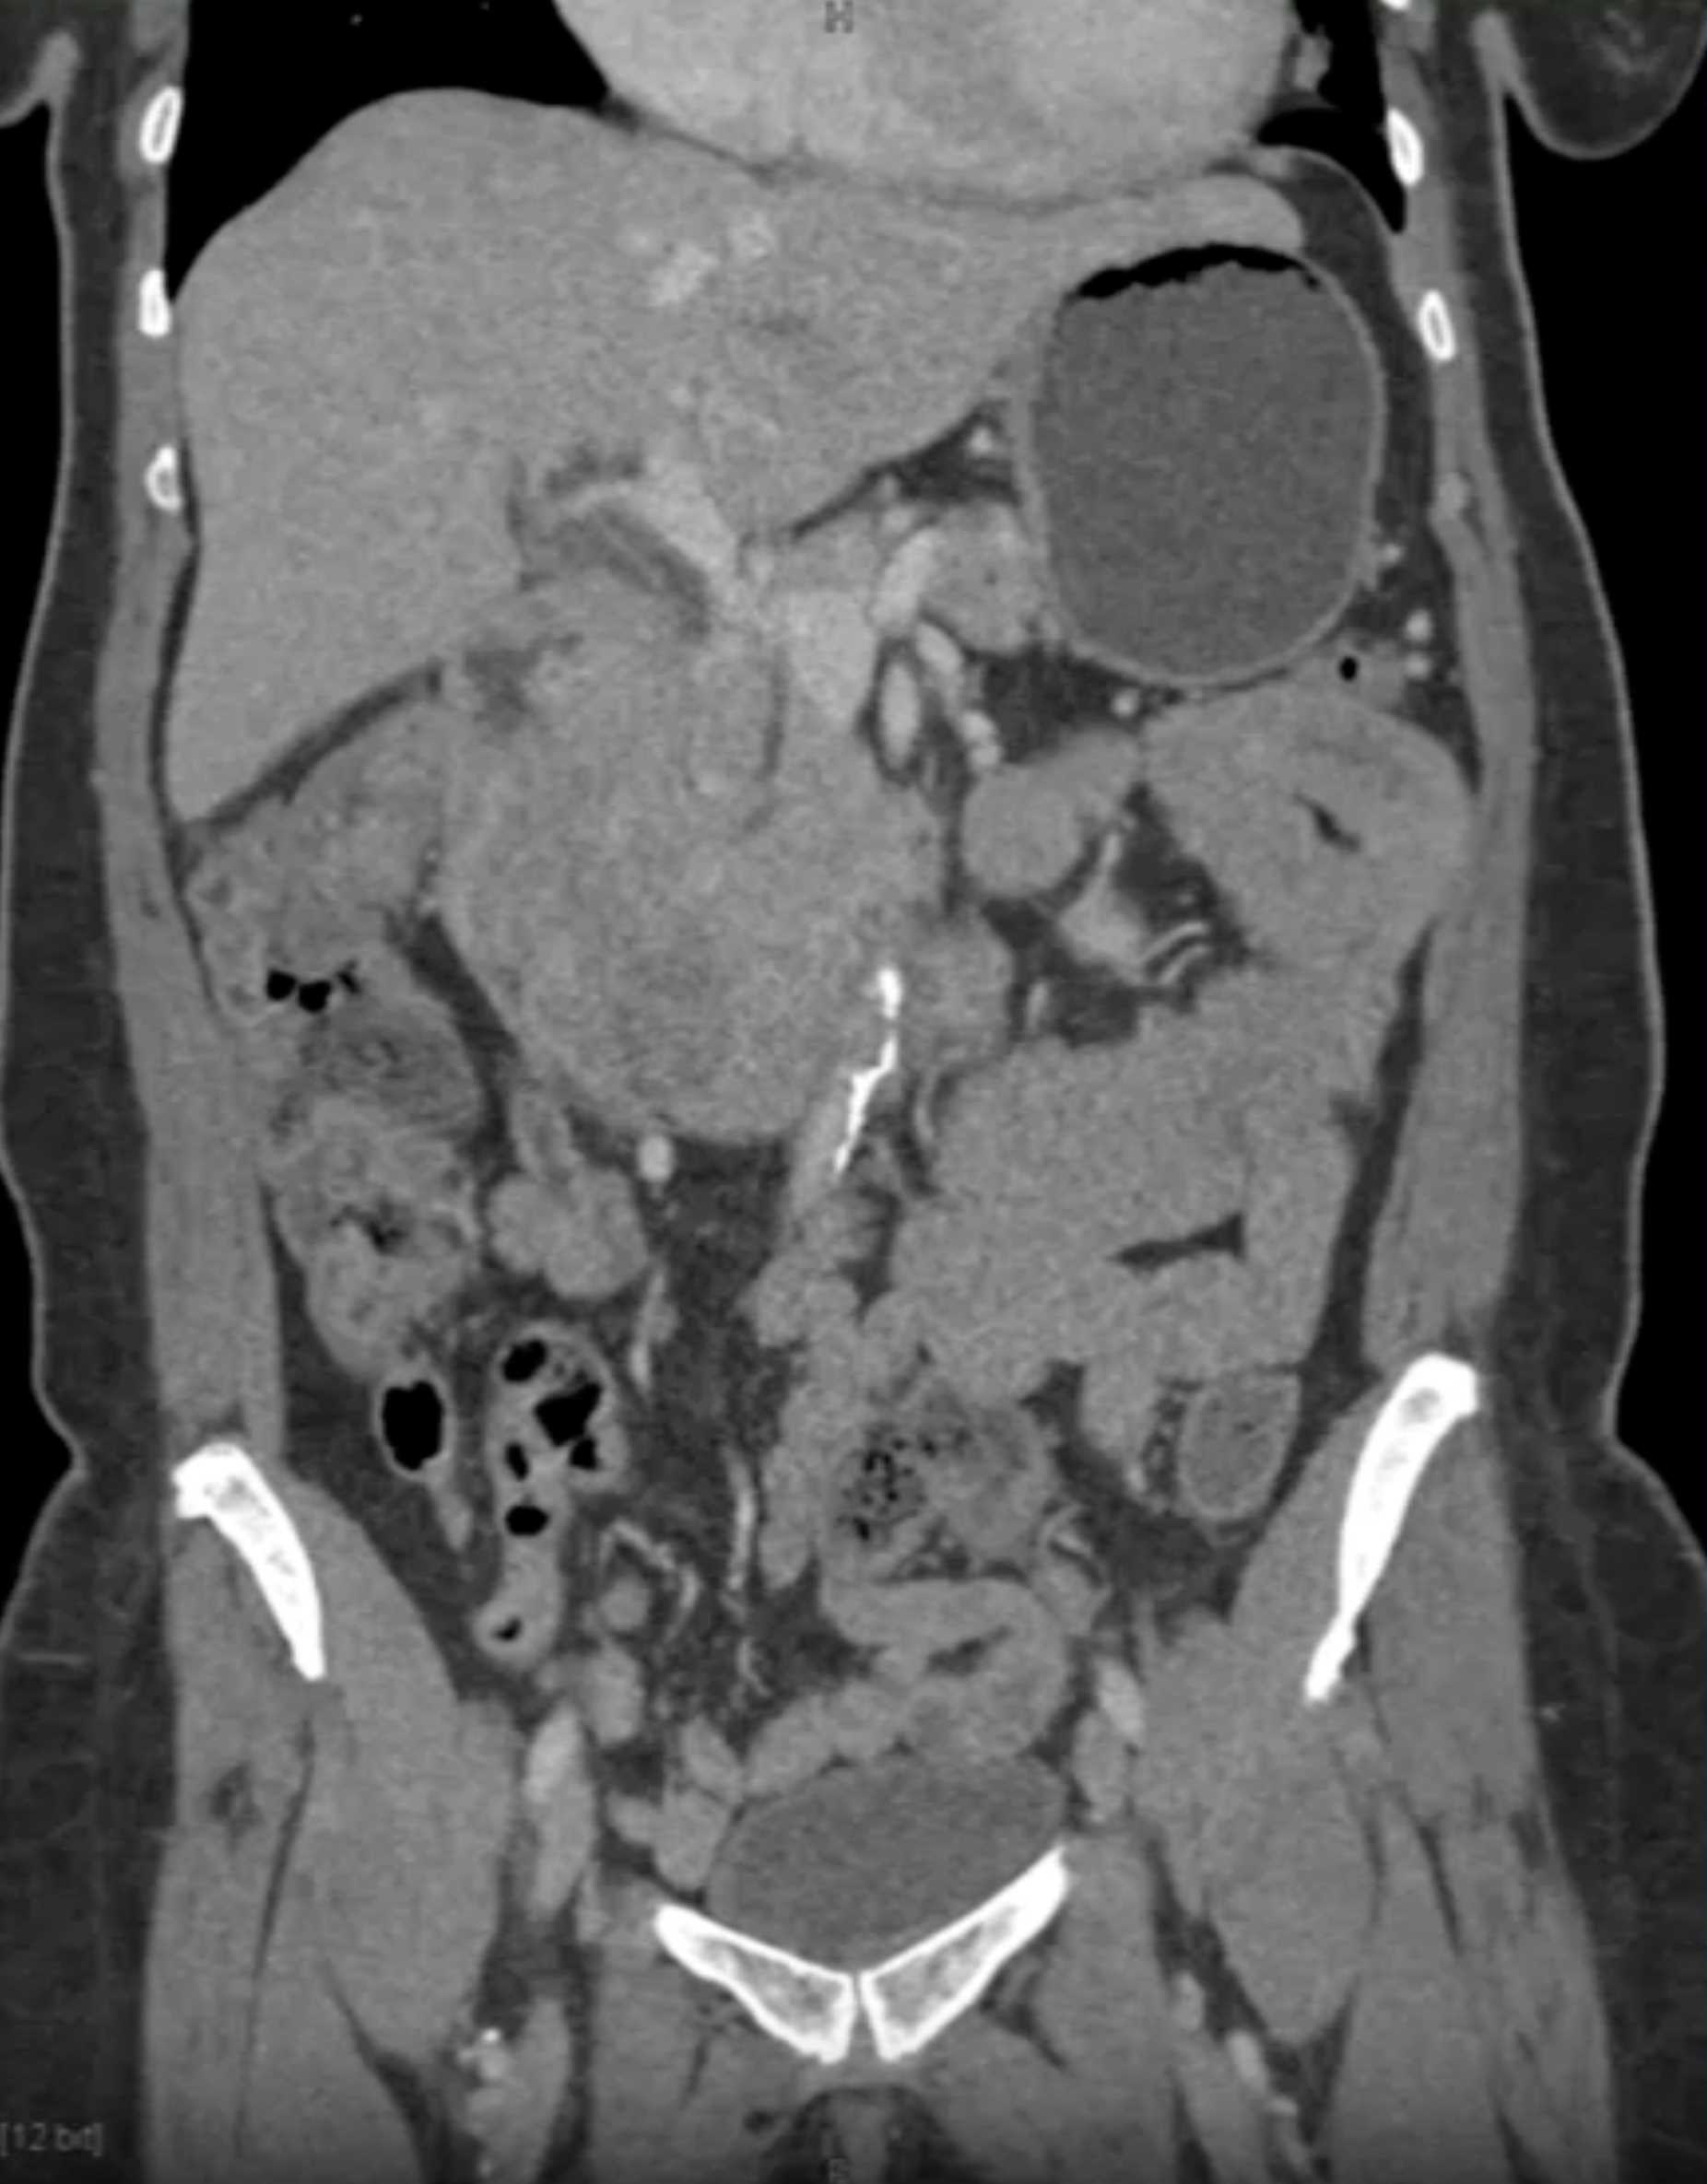

Lagre Gastric GIST Tumor